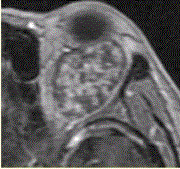

患者女,30岁,左眼球突出,运动障碍7个月。MRI平扫示左肌锥内等T信号影(下图)。增强扫描示均匀增强,眼肌、眼环正常。眼眶海绵状血管瘤MR表...

问题 患者女,30岁,左眼球突出,运动障碍7个月。MRI平扫示左肌锥内等T信号影(下图)。增强扫描示均匀增强,眼肌、眼环正常。 眼眶海绵状血管瘤MR表现是

选项 A.多位于肌锥外 B.为迂曲条状 C.T2加权像为低信号 D.T2加权像为高信号 E.病变信号不均匀 F.渐进性强化

答案 DF